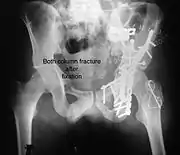

Posterior column and wall fracture as seen on 3D CT

Posterior column and wall fixed using screws and plates